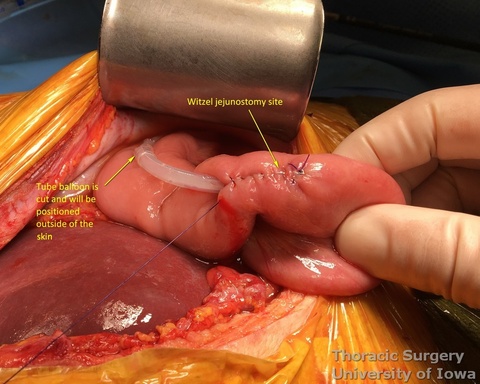

- 16 Fr feeding Witzel (KP, EA) or Stamm (JK) or jejunostomy is placed (see: Witzel feeding jejunostomy)